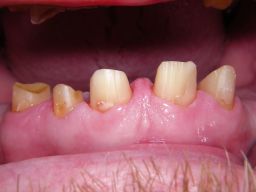

Das Hauptproblem dieses Falles lag im Oberkiefer - die über die Jahrzehnte abgeknirschten, kurzen Zähne erschweren Kronen, die durch eine Prothese belastet werden können. Die gewählte Lösung besteht darin, die Zähne nur rundherum zu beschleifen, aber nicht mehr zu kürzen und die Prothese mit einem Druckknopfsystem an die Zähne anzukoppeln, das ein "Spiel" aufweist, so daß die Prothese nicht als Hebelarm auf die schwachen Restzähne wirken kann. Rechts die beschliffenen Zähne kurz vorm Zementieren der Kronen.

Oberkieferrestzähne von vorne

Oberkieferrestzähne in Aufsicht

Oberkiefer vorm Zementieren